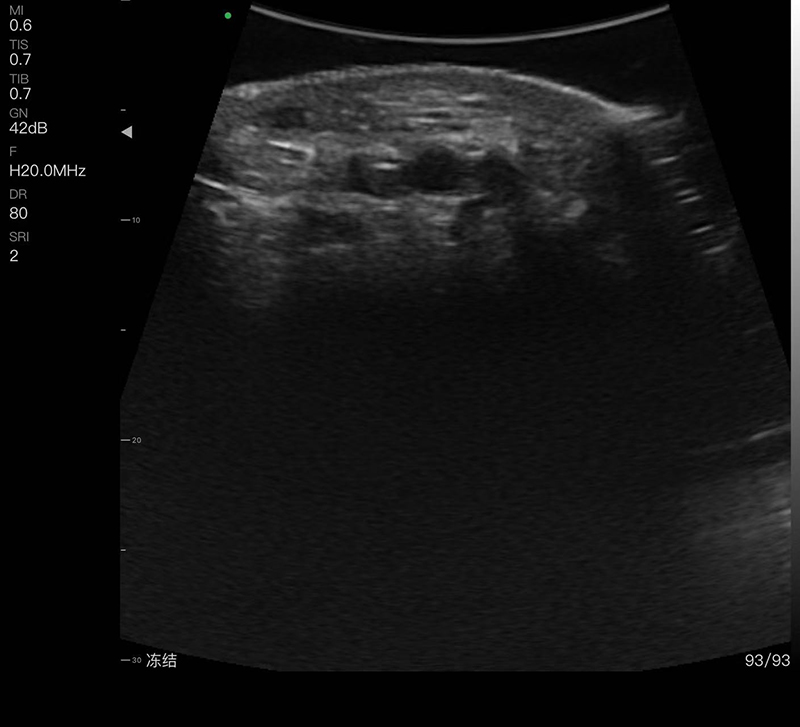

A must-have handheld ultrasound device with a fingertip probe that can be easily carried in your pocket. With a small handheld device, you can easily take pictures and images by placing the probe on your fingers, freeing your hands from the need to hold the probe and allowing you to hold other things. It is particularly suitable for surgery.

• Scanning Depth: 10/20/30/40mm, adjustable

• Display mode: B, B/M, Color, PDI, PW